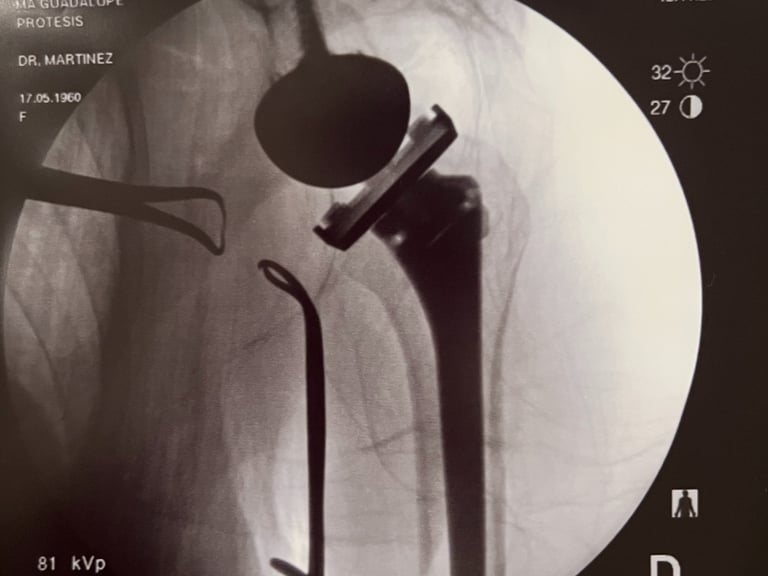

Control de radiografía de prótesis reversa de hombro.